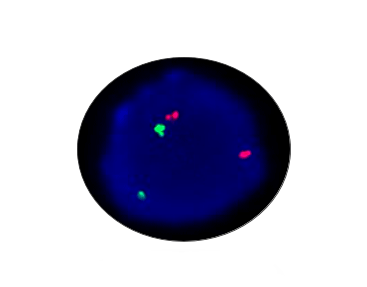

CHD1 Deletion

Probe Description: CHD1/5p15

Cat.No.: CF1044